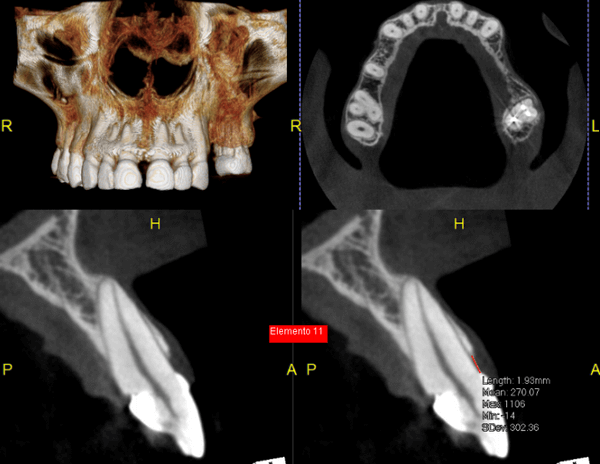

A Tomografia Computadorizada pela técnica do feixe cônico/cone beam (CBCT) introduziu um novo conceito de tomografia computadorizada na região bucomaxilofacial, que por meio da rápida aquisição volumétrica produz imagens com altíssimo grau de definição e fidelidade, além da redução na dose total de radiação emitida ao paciente.

Além disso, ocorre a minimização dos artefatos de imagem em relação à TC médica, o que torna possível a realização de imagens com qualidade diagnóstica e precisão sub-milimétrica, mesmo na presença de estruturas metálicas (restaurações, pinos/núcleos, aparelhos ortodônticos).